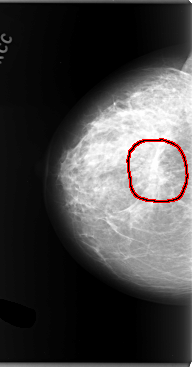

C_0101_1.RIGHT_CC

RIGHT_CC LINES 5864 PIXELS_PER_LINE 3064 BITS_PER_PIXEL 12 RESOLUTION 50 OVERLAY

FILE: C_0101_1.RIGHT_CC.OVERLAY

TOTAL_ABNORMALITIES 1

ABNORMALITY 1

LESION_TYPE MASS SHAPE ARCHITECTURAL_DISTORTION MARGINS SPICULATED

ASSESSMENT 5

SUBTLETY 5

PATHOLOGY MALIGNANT

TOTAL_OUTLINES 1

BOUNDARY